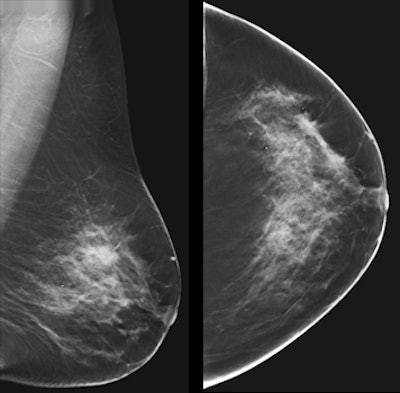

A 63-year-old woman with bilateral breast pain for two months. Both breasts were normal on clinical evaluation. In the outer quadrant of the left breast, a subtle spiculated mass, measuring 16 mm, is seen on craniocaudal view that is not well-visualized on mediolateral oblique view, but it is better demonstrated on tomosynthesis. Courtesy of Dr. Fiona Gilbert, University of Cambridge, U.K. Originally published in ECR Today 2017.

A 63-year-old woman with bilateral breast pain for two months. Both breasts were normal on clinical evaluation. In the outer quadrant of the left breast, a subtle spiculated mass, measuring 16 mm, is seen on craniocaudal view that is not well-visualized on mediolateral oblique view, but it is better demonstrated on tomosynthesis. Courtesy of Dr. Fiona Gilbert, University of Cambridge, U.K. Originally published in ECR Today 2017."It's the most promising tool we have," said breast imaging pioneer Dr. Sylvia Heywang-Köbrunner of Breast Diagnostics Munich in a symposium dedicated to breast health.

DBT's potential can't be denied and its superior sensitivity when compared to digital mammography isn't in doubt, she asserted.But a number of issues need further study, including whether DBT is finding clinically important cancers, the logistics of incorporating the technology into department workflow, and reducing reading time -- which can be two to four times longer than digital mammography.

"Tomosynthesis is the better modality when compared to digital mammography," saidHeywang-Köbrunner. "But is it ready now to replace [2D mammography] for screening? No. We're lacking information, particularly about its interval cancer performance."